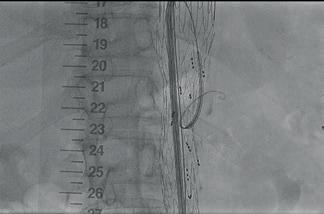

“Critical” importance of lifelong surveillance after EVAR headlines newly published 10-year ENGAGE data

Ten-year data highlight the long-term efficacy and durability of the Endurant stent graft (Medtronic) in abdominal aortic aneurysm (AAA) patients who survived beyond five years post-enrolment in the ENGAGE registry. However, researchers also draw attention to the incidence of late events in this extended follow-up cohort, which they say underscores the need for lifelong surveillance. These findings were recently published online in the European Journal of Vascular and Endovascular Surgery (EJVES).

ENGAGE IS A MEDTRONIC-SPONSORED, observational, multicentre, non-randomised, prospective global registry designed to shed light on the long-term outcomes of endovascular aneurysm repair (EVAR). In their EJVES paper, Hence Verhagen (Erasmus University Medical Centre Rotterdam, Rotterdam, the Netherlands) and a team of coinvestigators from across Europe, the USA and Canada note that the registry will be the first to report long-term outcomes of real-world, global AAA patients with the Endurant stent graft.

Verhagen and colleagues share that inclusion criteria for the registry were “minimal” and allowed for the incorporation of patients who fell outside the instructions for use guidance. Exclusion criteria, meanwhile, were “high probability of non-adherence to follow-up requirements, or concurrent participation in another trial that could confound results”. The authors note that clinical and imaging data were continuously collected to evaluate treatment efficacy through 10 years.

cohort. The remaining 873 patients made up a nonextended follow-up cohort.

In EJVES, the authors report the continued longterm efficacy and durability of the Endurant stent graft. They share that freedom from site-reported all-cause mortality and clinical event committee (CEC)-adjudicated aneurysm-related mortality for the extended follow-up cohort was 75.7% and 97.3% through 10 years, respectively.

Furthermore, through 10 years, Verhagen et al note that each rate for freedom from aneurysm-related rupture (96.2%) and aneurysm-related interventions (71.4%) was comparable with the respective rate through the first five years.

Among several other datapoints, the authors detail that late re-interventions (n=72) were associated with type Ia endoleaks (18/72), type II endoleaks (18/72), and type Ib endoleaks, adding that, at 10 years, 64.1% of patients exhibited sac regression, 19.2% were sac stable, and 16.8% had sac expansion.

Of the 1,263 patients enrolled in the ENGAGE registry, Verhagen and colleagues state that 390 reconsented for follow-up from more than five through 10 years, constituting an extended follow-up

Verhagen and colleagues do highlight some limitations of their paper. “Potential bias was introduced as a subset of patients and sites did not reconsent from the original ENGAGE population

In the conclusion of their paper, the authors also draw attention to the fact that “this study was the first to demonstrate long-term performance and durability of the Endurant stent graft for aortic aneurysm treatment.” They also home in on the incidence of late events. “Different factors led to reintervention in the later years,” they state, noting that this supports current recommendations of lifelong surveillance.

“The authors suggest that lifelong surveillance is critical for EVAR patients due to the incidence of late events,” Verhagen and colleagues write.